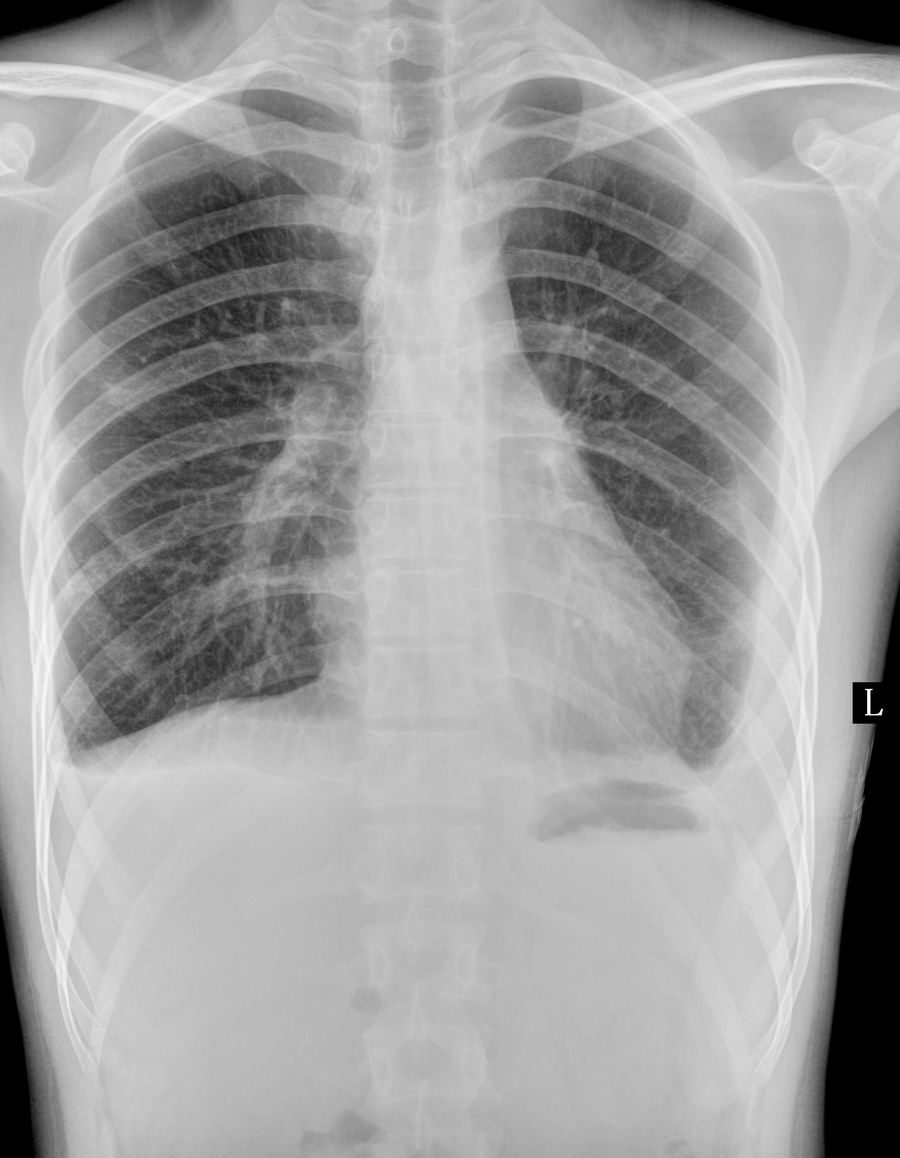

以下是引用一生何求在2010-5-12 9:35:00的发言:[br]两次片子对比可见左侧胸腔积液量有所减少,而右侧则增多;右肺小病灶考虑为一个比较稳定的病灶,有向纤维化或钙化方向发展的趋势 最终转变为陈旧性病变。[br]建议随诊复查。

以下是引用zhanggenliang在2010-5-12 16:49:00的发言:[br]右肺的高密度影应该是中叶吧。请问治疗过程。是抽水呢?还是抗结核治疗,还是抗炎。如果抽水应该化验,因为化验鉴别明了,如果抗结核就不用说了。如果是考大家,只能说影像较支持结核